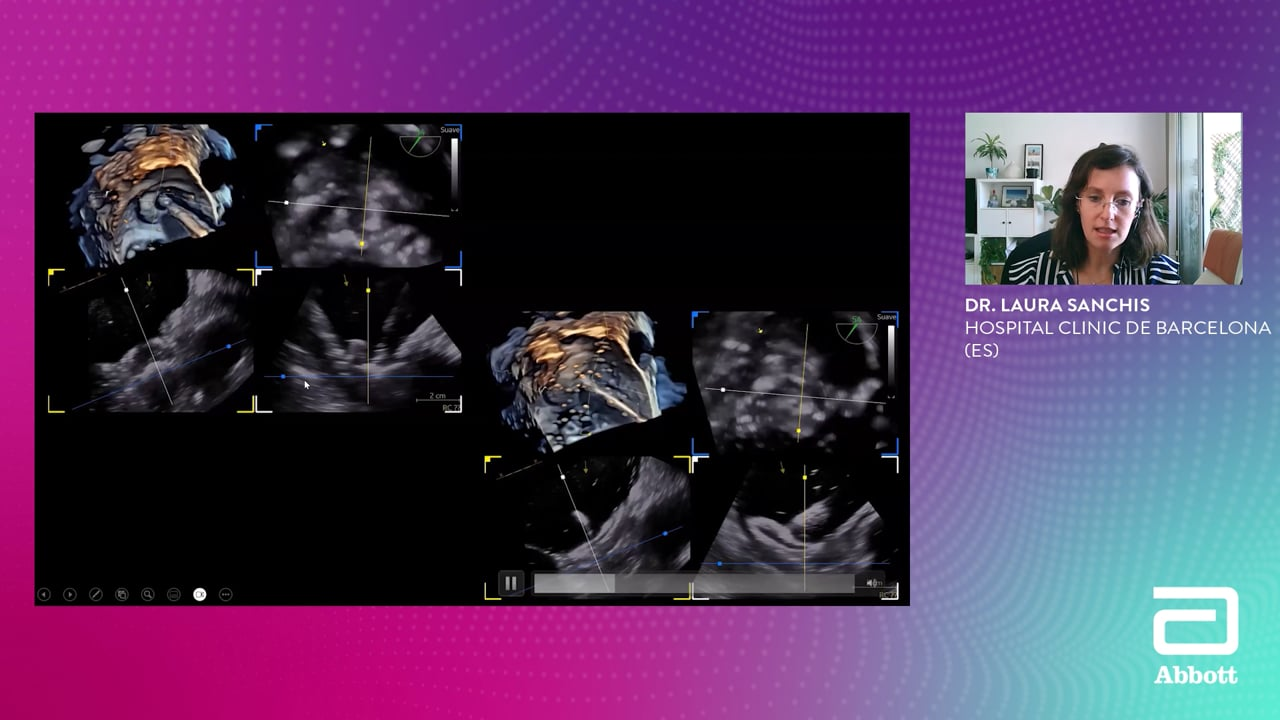

Left Atrial Appendage Occlusion (LAAO)

Focus to Left Atrial Appendage Occlusion, this session allow to interact with experts as they address echo screening, interventional guiding, and complication management for LAAO patients.